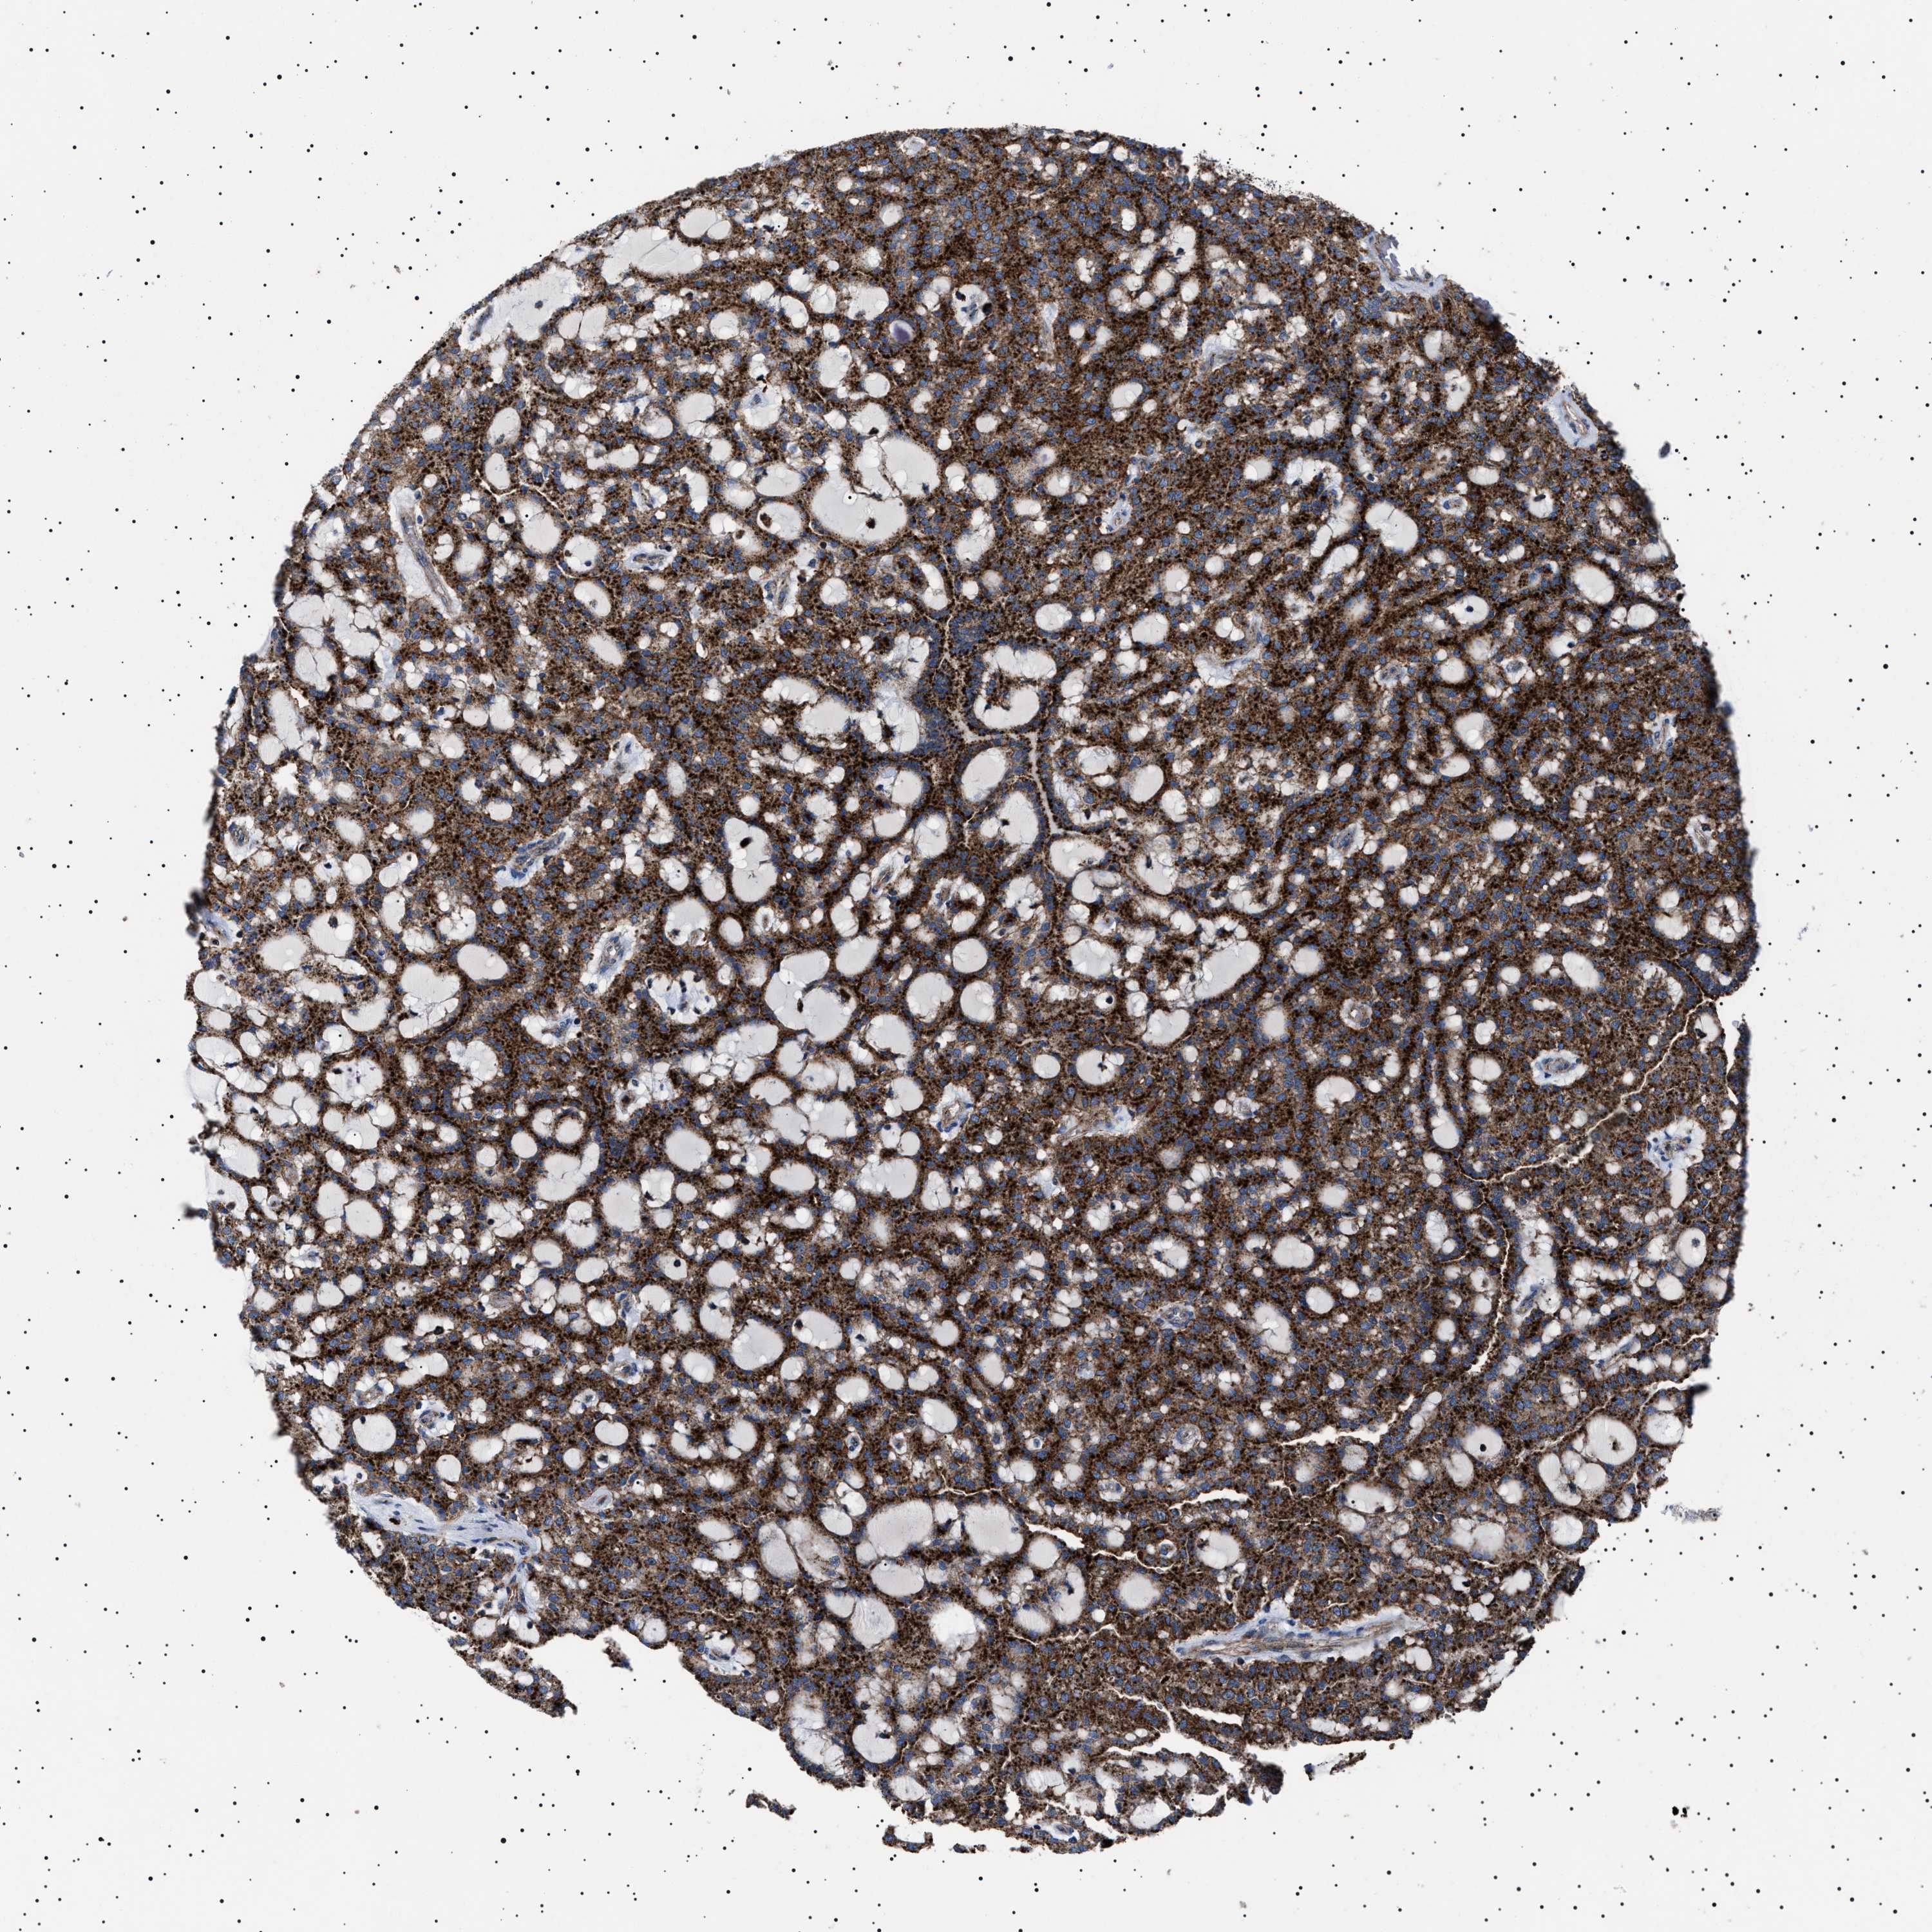

KIDNEY RENAL CLEAR CELL CARCINOMA (TCGA) - Interactive survival scatter ploti

The Survival Scatter plot shows the clinical status (i.e. dead or alive) for all individuals in the patient cohort, based on the same data that underlies the corresponding Kaplan-Meier plots. Patients that are alive at last time for follow-up are shown in blue and patients who have died during the study are shown in red.

The x-axis shows the expression levels (FPKM) of the investigated gene in the tumor tissue at the time of diagnosis. The y-axis shows the follow-up time after diagnosis (years). Both axes are complimented with kernel density curves demonstrating the data density over the axes. The top density plot shows the expression levels (FPKM) distribution among dead (red) and alive patients (blue). The right density plot shows the data density of the survived years of dead patients with high and low expression levels respectively, stratified using the cutoff indicated by the vertical dashed line through the Survival Scatter plot. This cutoff is automatically defined based on the FPKM cutoff that minimizes the p-score. The cutoff can be changed by dragging the vertical line or by entering a cutoff value in the square labeled "Current cut-off".

Under the Survival Scatter plot the p-score landscape (black curve; left axis) is shown together with dead median separation (red curve; right axis). Dead median separation is the difference in median mRNA expression between patients who have died with high and low expression, respectively. It is calculated as follows: median FPKM expression of dead patients with high expression - median FPKM expression of dead patients with low expression. This is intended to aid the user in visually exploring custom cutoffs and the associated p-scores and dead median separation.

Individual patient data is displayed and can be filtered by clicking on one or more of the category buttons on the top of the page. Categories describing expression level and patient information include: high, low, alive, dead, female, male and tumor stages. The scale of the x-axis can be toggled between linear and log-scale by clicking on the "x log" button. Mouse-over function shows TCGA ID, patient information and mRNA expression (FPKM) for each patient.

& Survival analysisi

Kaplan-Meier plots summarize results from analysis of correlation between mRNA expression level and patient survival. Patients were divided based on level of expression into one of the two groups "low" (under cut off) or "high" (over cut off). X-axis shows time for survival (years) and y-axis shows the probability of survival, where 1.0 corresponds to 100 percent.

NEU1 is potential prognostic, high expression is favorable in Kidney Renal Clear Cell Carcinoma (TCGA)

Best expression cut offi

Based on the FPKM value of each gene, patients were classified into two groups and association between prognosis (survival) and gene expression (FPKM) was examined. The best expression cut-off refers the FPKM value that yields maximal difference with regard to survival between the two groups at the lowest log-rank P-value. Best expression cut-off was selected based on survival analysis .

When clicking on this number, the vertical dashed line indicating cut-off, the interactive survival plot, and the Kaplan-Meier curve will be adjusted to show results based on the best expression cut-off.

: 1.86

TCGA RNA samplesi

RNA-seq data is reported as average FPKM (number Fragments Per Kilobase of exon per Million reads), generated by the The Cancer Genome Atlas (TCGA) .

Normal distribution across the dataset is visualized with box plots, shown as median and 25th and 75th percentiles. Points are displayed as outliers if they are above or below 1.5 times the interquartile range. FPKM values of the individual samples are presented next to the box plot.

Average pTPM 1.3

Number of samples 521